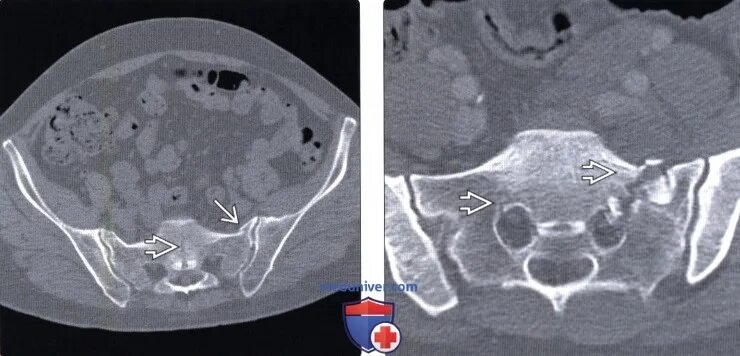

Метастазы в крестце